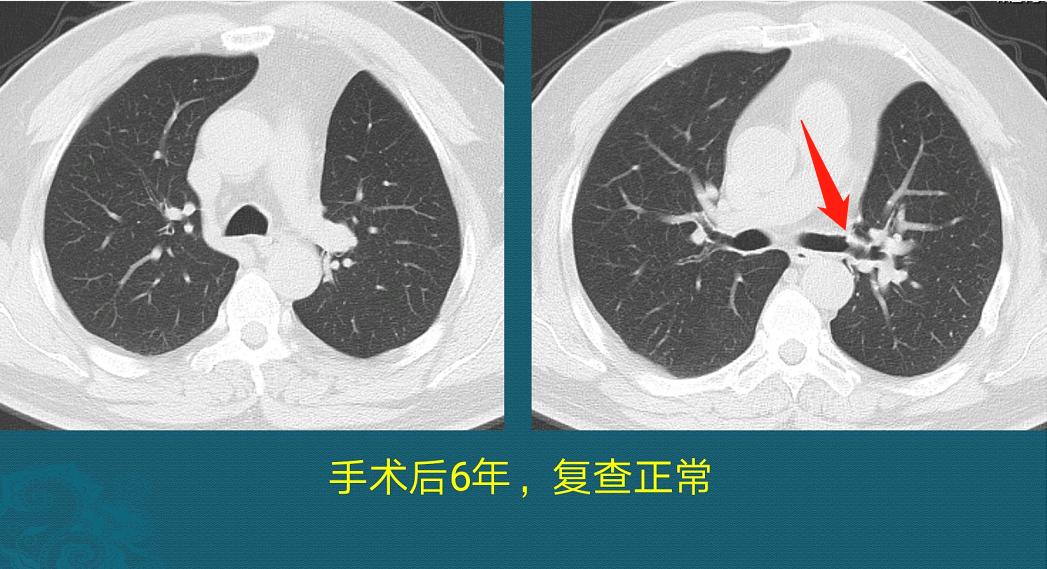

一晃6年过去,最后一次复查显示恢复很好,没有复发,肺功能也正常:

之后就抓紧住进胸外科,全面检查后没有发现其他转移播散,做了左肺上叶切除和淋巴结清扫,病理是中分化肺鳞癌,清扫17枚淋巴结没有转移,手术后做了化疗,之后定期复查。